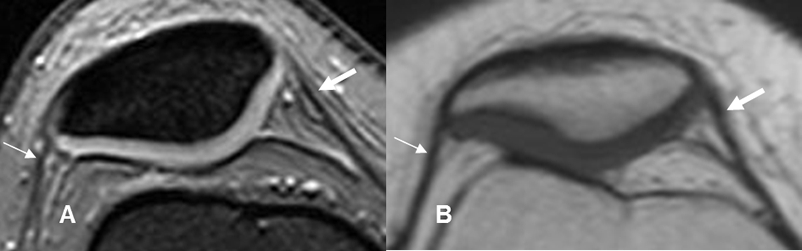

Fig 30. Meniscos normales.

A: RM coronal en STIR. Menisco interno (Flecha delgada) y menisco externo (Flecha gruesa). B: RM axial en T2. Menisco interno (Flechas delgadas) y Externo (Flechas gruesas).

Fig 31. Meniscos normales en ArtroRM.

A: ArtroRM sagital en STIR y B: ArtroRM axial en STIR. Meniscos normales, rodeados por la mezcla de contraste hiperintensa.